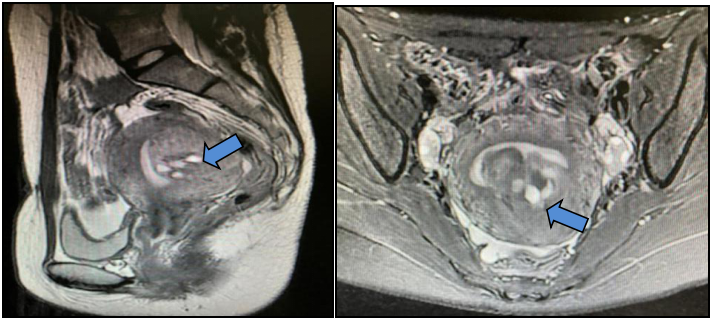

以“子宫肌瘤剔除术后14个月,子宫肌瘤复发11个月”再次返院就诊,盆腔增强磁共振成像(MRI)提示:子宫体大小约7.4 cm×6.8 cm×8.0 cm(含病变),子宫肌瘤大小约5.0 cm×4.8 cm×4.6 cm,突入宫腔,其内多发囊变,考虑子宫粘膜下肌瘤。

盆腔增强MRI提示子宫体明显增大,约9.2 cm×12.3 cm×9.5 cm(含病变),宫腔受压,子宫肌壁、黏膜下及浆膜下见多发结节及肿块(约10个),宫体前壁上段一结节突入宫腔,直径1.3 cm,最大者位于左后壁,大小约7.6 cm×7.9 cm×10.0 cm;DWI多发高信号,考虑子宫富于细胞型肌瘤,血供丰富,生长活跃。